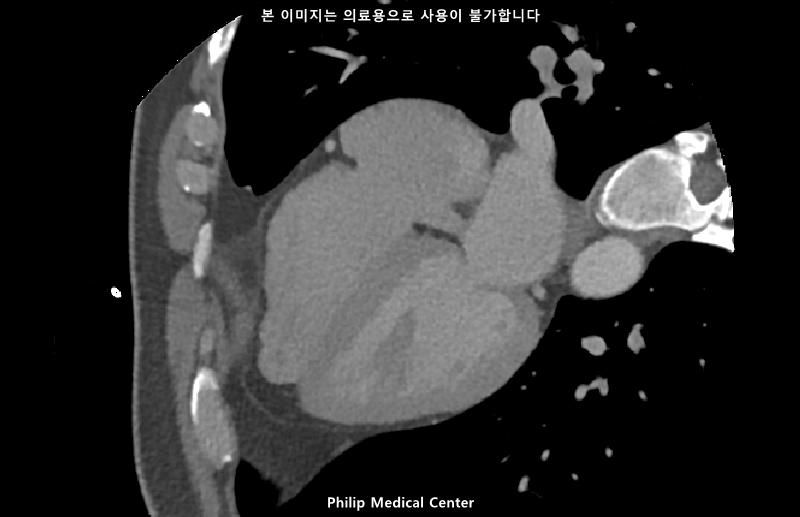

• 2번 째 사진

• 올리신 사진들을 통해서는 폐를 평가할 수 없습니다.

우측 폐첨부에 경미한 섬유성변화와 우중엽에 약 3mm크기의 결절이라는 것은 이상 소견이긴 하지만 보통 경과관찰을 하는 소견입니다.